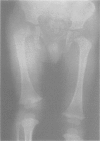

A 12 year old girl with the Poland syndrome and the 'morning glory' syndrome is described. The patient presented with absence of the left pectoralis major muscle, hypoplasia of the left arm, symbrachydactyly, and ipsilateral coloboma of the optic disc. This is the first report of the association of these two congenital anomalies.